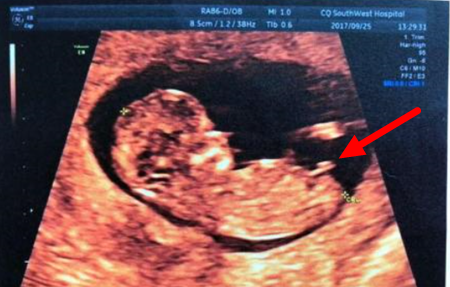

(男宝nub点)

NT检查大部分的妈妈都是在孕期12周左右做的,这时候宝宝的性征已经发育明显,如果能看到超声的图片,其实是可以看出男女的,我们在图片上可以看到具有性征的一些身体特点,男孩的特征点与身体呈45度角,还多一些,而女孩儿的特征点几乎和躯体平行。还有就是如果是男宝宝,屁股位置会微微上翘,后背脊柱成圆弧状,因为要留空间发育前列腺,相反,女宝宝后背脊柱就相对就平一些。

Boy nub: The nub is at a much steeper angle upwards, indicating that this baby is a boy.

小肿块以一个陡峭的角度向上指,显示这个胎儿是个男孩。